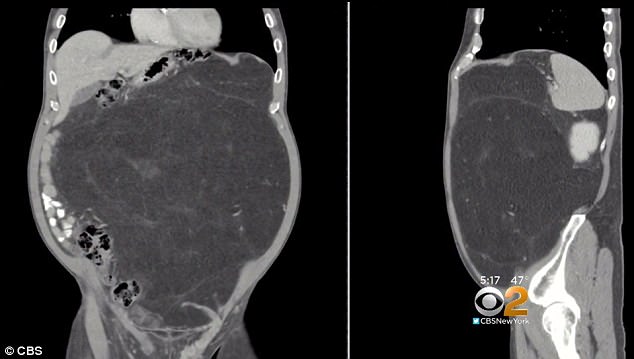

Томография показала, что большую часть брюшной полости Дэли занимает огромная липосаркома. Новообразование росло в его животе около 10 лет. Как правило, опухоль замечают быстрее, поэтому липосаркома таких размеров - редкость.

Операция, во время которой у Дэли удалили опухоль и поглощенную ей почку, продолжалась шесть часов. Поскольку обычно липосаркомы распространяются медленно и не сопровождаются метастазами, врачи дают хороший прогноз.